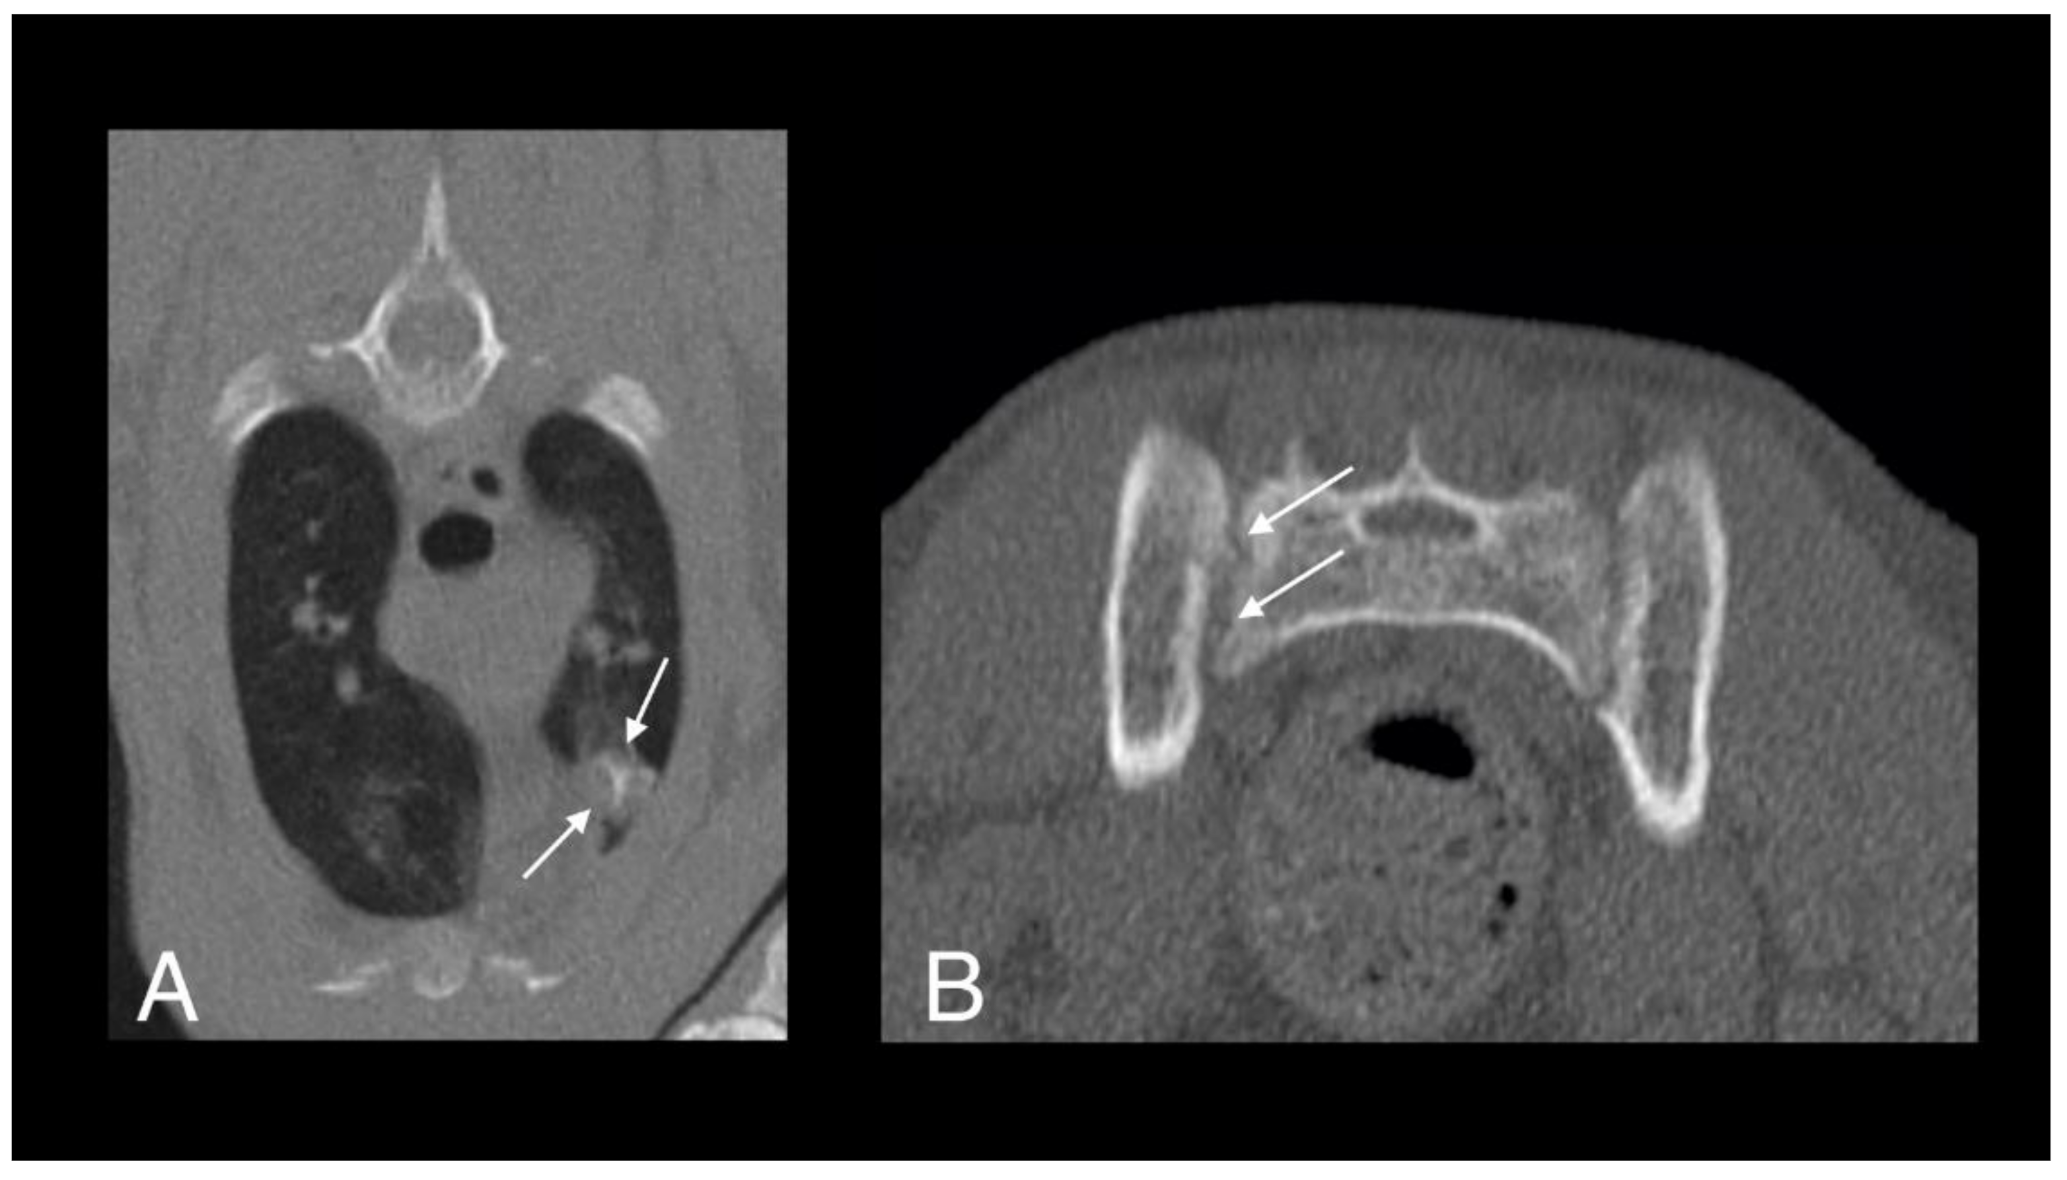

- Bennett, A.D.; Lalor, S.; Schwarz, T.; Gunn-Moore, D.A. Radiographic findings in cats with mycobacterial infections. J. Feline Med. Surg. 2011, 13, 718–724. [Google Scholar] [CrossRef] [PubMed]

- Major, A.; Holmes, A.; Warren-Smith, C.; Lalor, S.; Littler, R.; Schwarz, T.; Gunn-Moore, D. Computed tomographic findings in cats with mycobacterial infection. J. Feline Med. Surg. 2016, 18, 510–517. [Google Scholar] [CrossRef]

- Major, A.; O’Halloran, C.; Holmes, A.; Lalor, S.; Littler, R.; Spence, S.; Schwarz, T.; Gunn-Moore, D. Use of computed tomography imaging during long-term follow-up on nine feline tuberculosis cases. J. Feline Med. Surg. 2018, 20, 189–199. [Google Scholar] [CrossRef]